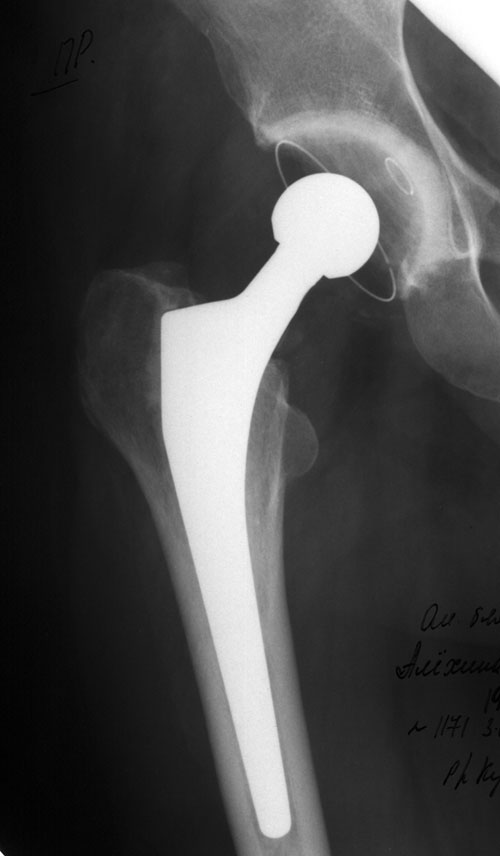

Нашей коллеге (оперирующая врач-гинеколог) 3 года назад произвели тотальное эндопротезирование правого тазобедренного сустава протезом <Протек> фирмы <Зульцер>.На сегодняшний день жалоб нет. Продолжает работать по специальности, двигаться в течение дня приходится достаточно много.Вопрос таков: спустя 3 года после подобной операции какая разрешена нагрузка (сколько ~ км в день), какова нужна реабилитация и как часто. Вообщем, нужны рекомендации по образу жизни (что можно, а чего нельзя). А также очень просила коллега подсказать приблизительный комплекс ЛФК или дать ссылку на подобную информацию.В приложении Rg от 03.01.2003 г. и история болезни в архиве zip из стационара, где оперировали.Заранее сильно благодарю,с уважением,Клоков Александр.

Total hip replacement is a surgical procedure for replacing the hip joint. This joint is composed of two parts - the hip socket (acetabulum, a cup-shaped bone in the pelvis) and the "ball" or head of the thigh bone (femur).

During the surgical procedure, these two parts of the hip joint are removed and replaced with smooth artificial surfaces.

The artificial socket is made of high-density plastic, while the artificial ball with its stem is made of a strong stainless metal.

These artificial pieces are implanted into healthy portions of the pelvis and thigh bones and affixed with a bone cement (methyl methacrylate).